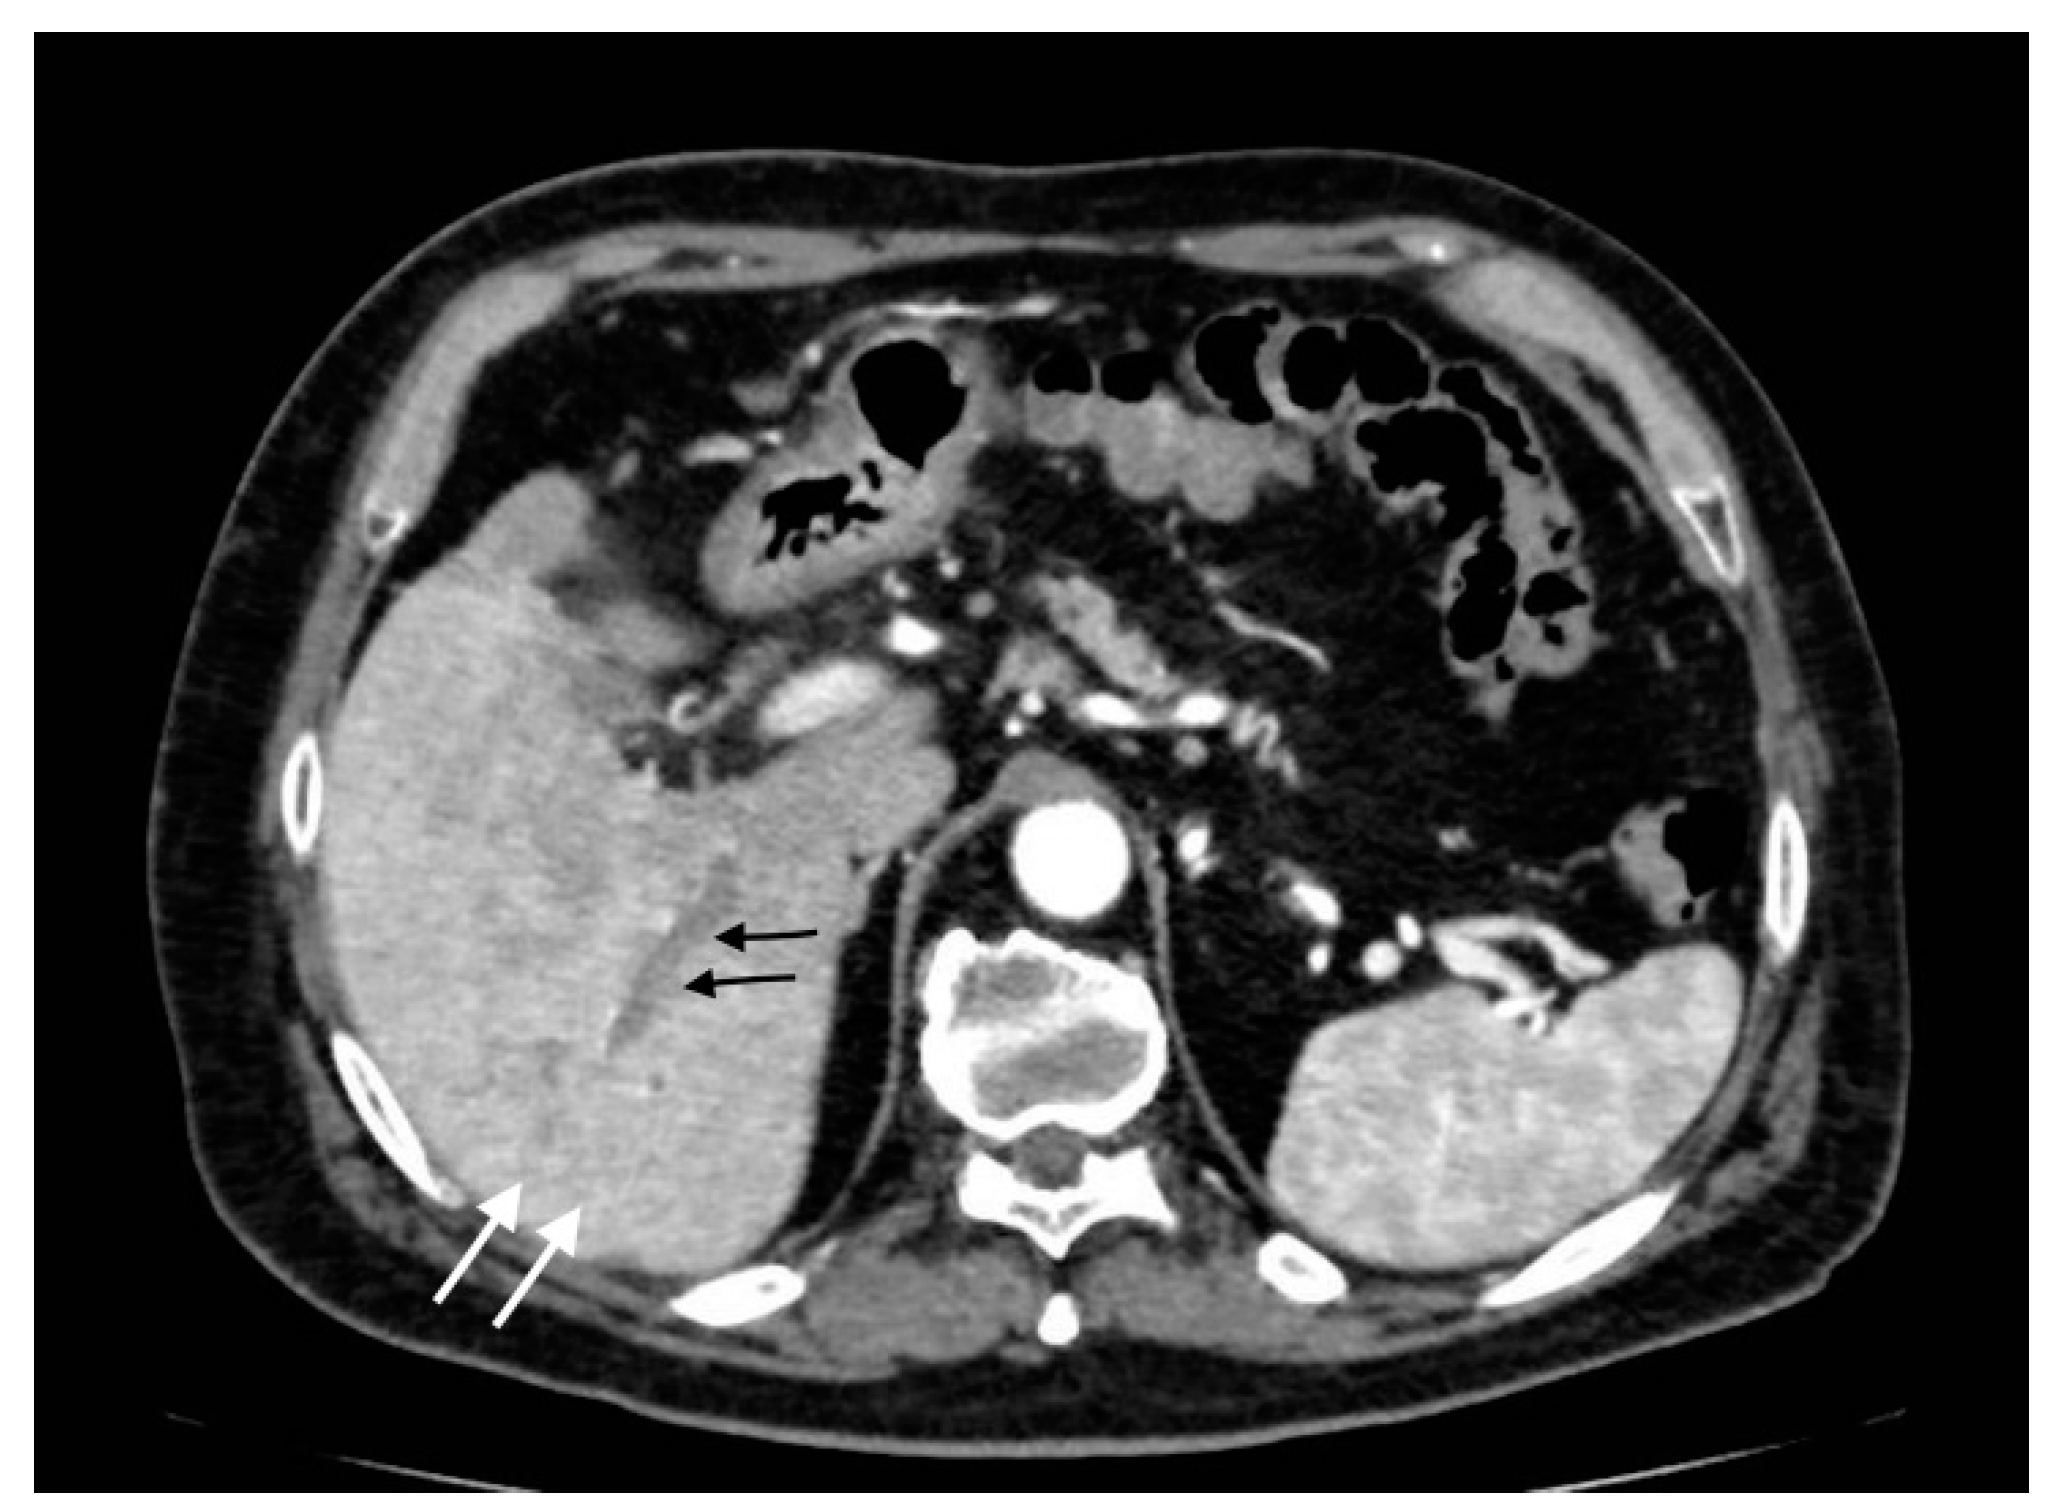

Figure 1.

Acute uncomplicated calculous cholecystitis: (a) overdistended gallbladder with diffuse wall thickening and hyperemia (white arrows) and pericholecystic fluid (arrowheads), (b) pericholecystic parenchymal enhancement (black arrows).